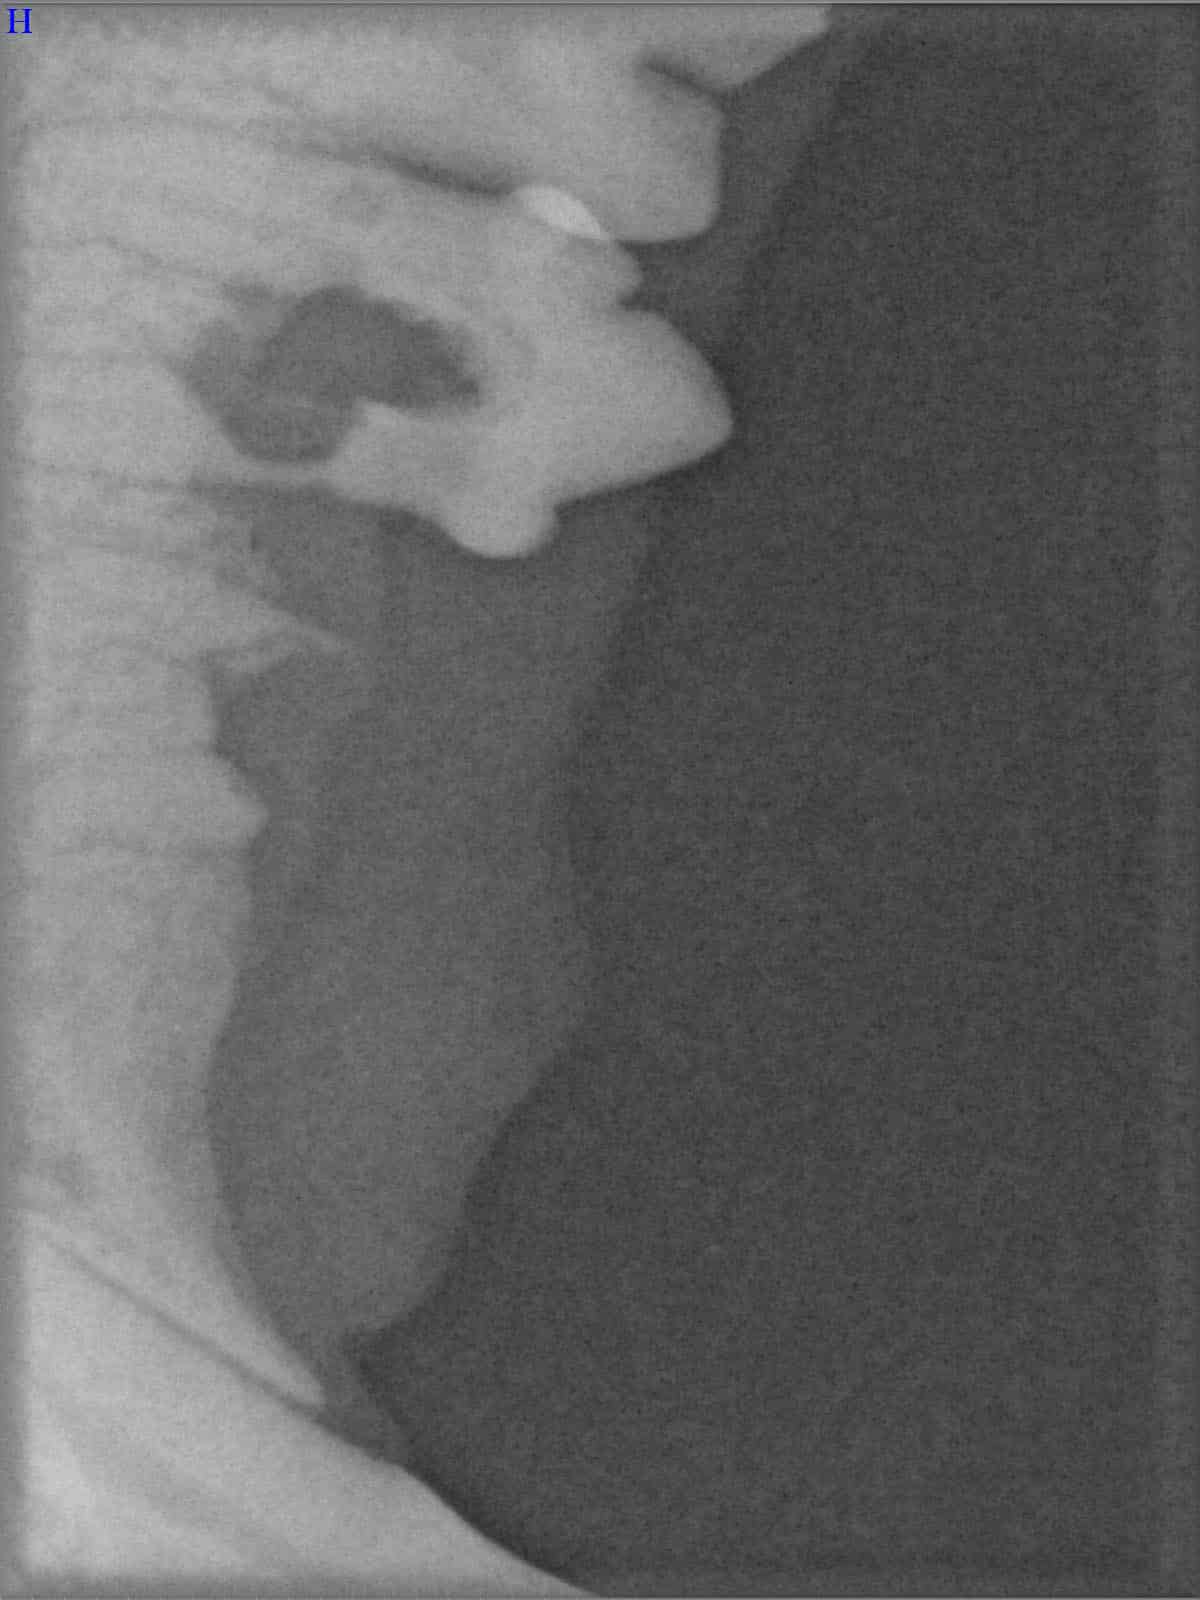

Ein entscheidender Baustein der FORL-Diagnostik ist das dentale Röntgen. Viele Läsionen sind von außen nicht sichtbar und lassen sich ausschließlich mithilfe moderner Röntgentechnik erkennen. In der Hamburger Praxis kommt digitales Dentalröntgen zum Einsatz, das detailreiche Aufnahmen bei geringer Strahlenbelastung ermöglicht. So kann FORL bereits in frühen Stadien diagnostiziert werden.

Das sehen Sie von außen – so sieht es auf den Röntgenbildern aus.

FORL Katze Röntgenbild

Röntgenbilder